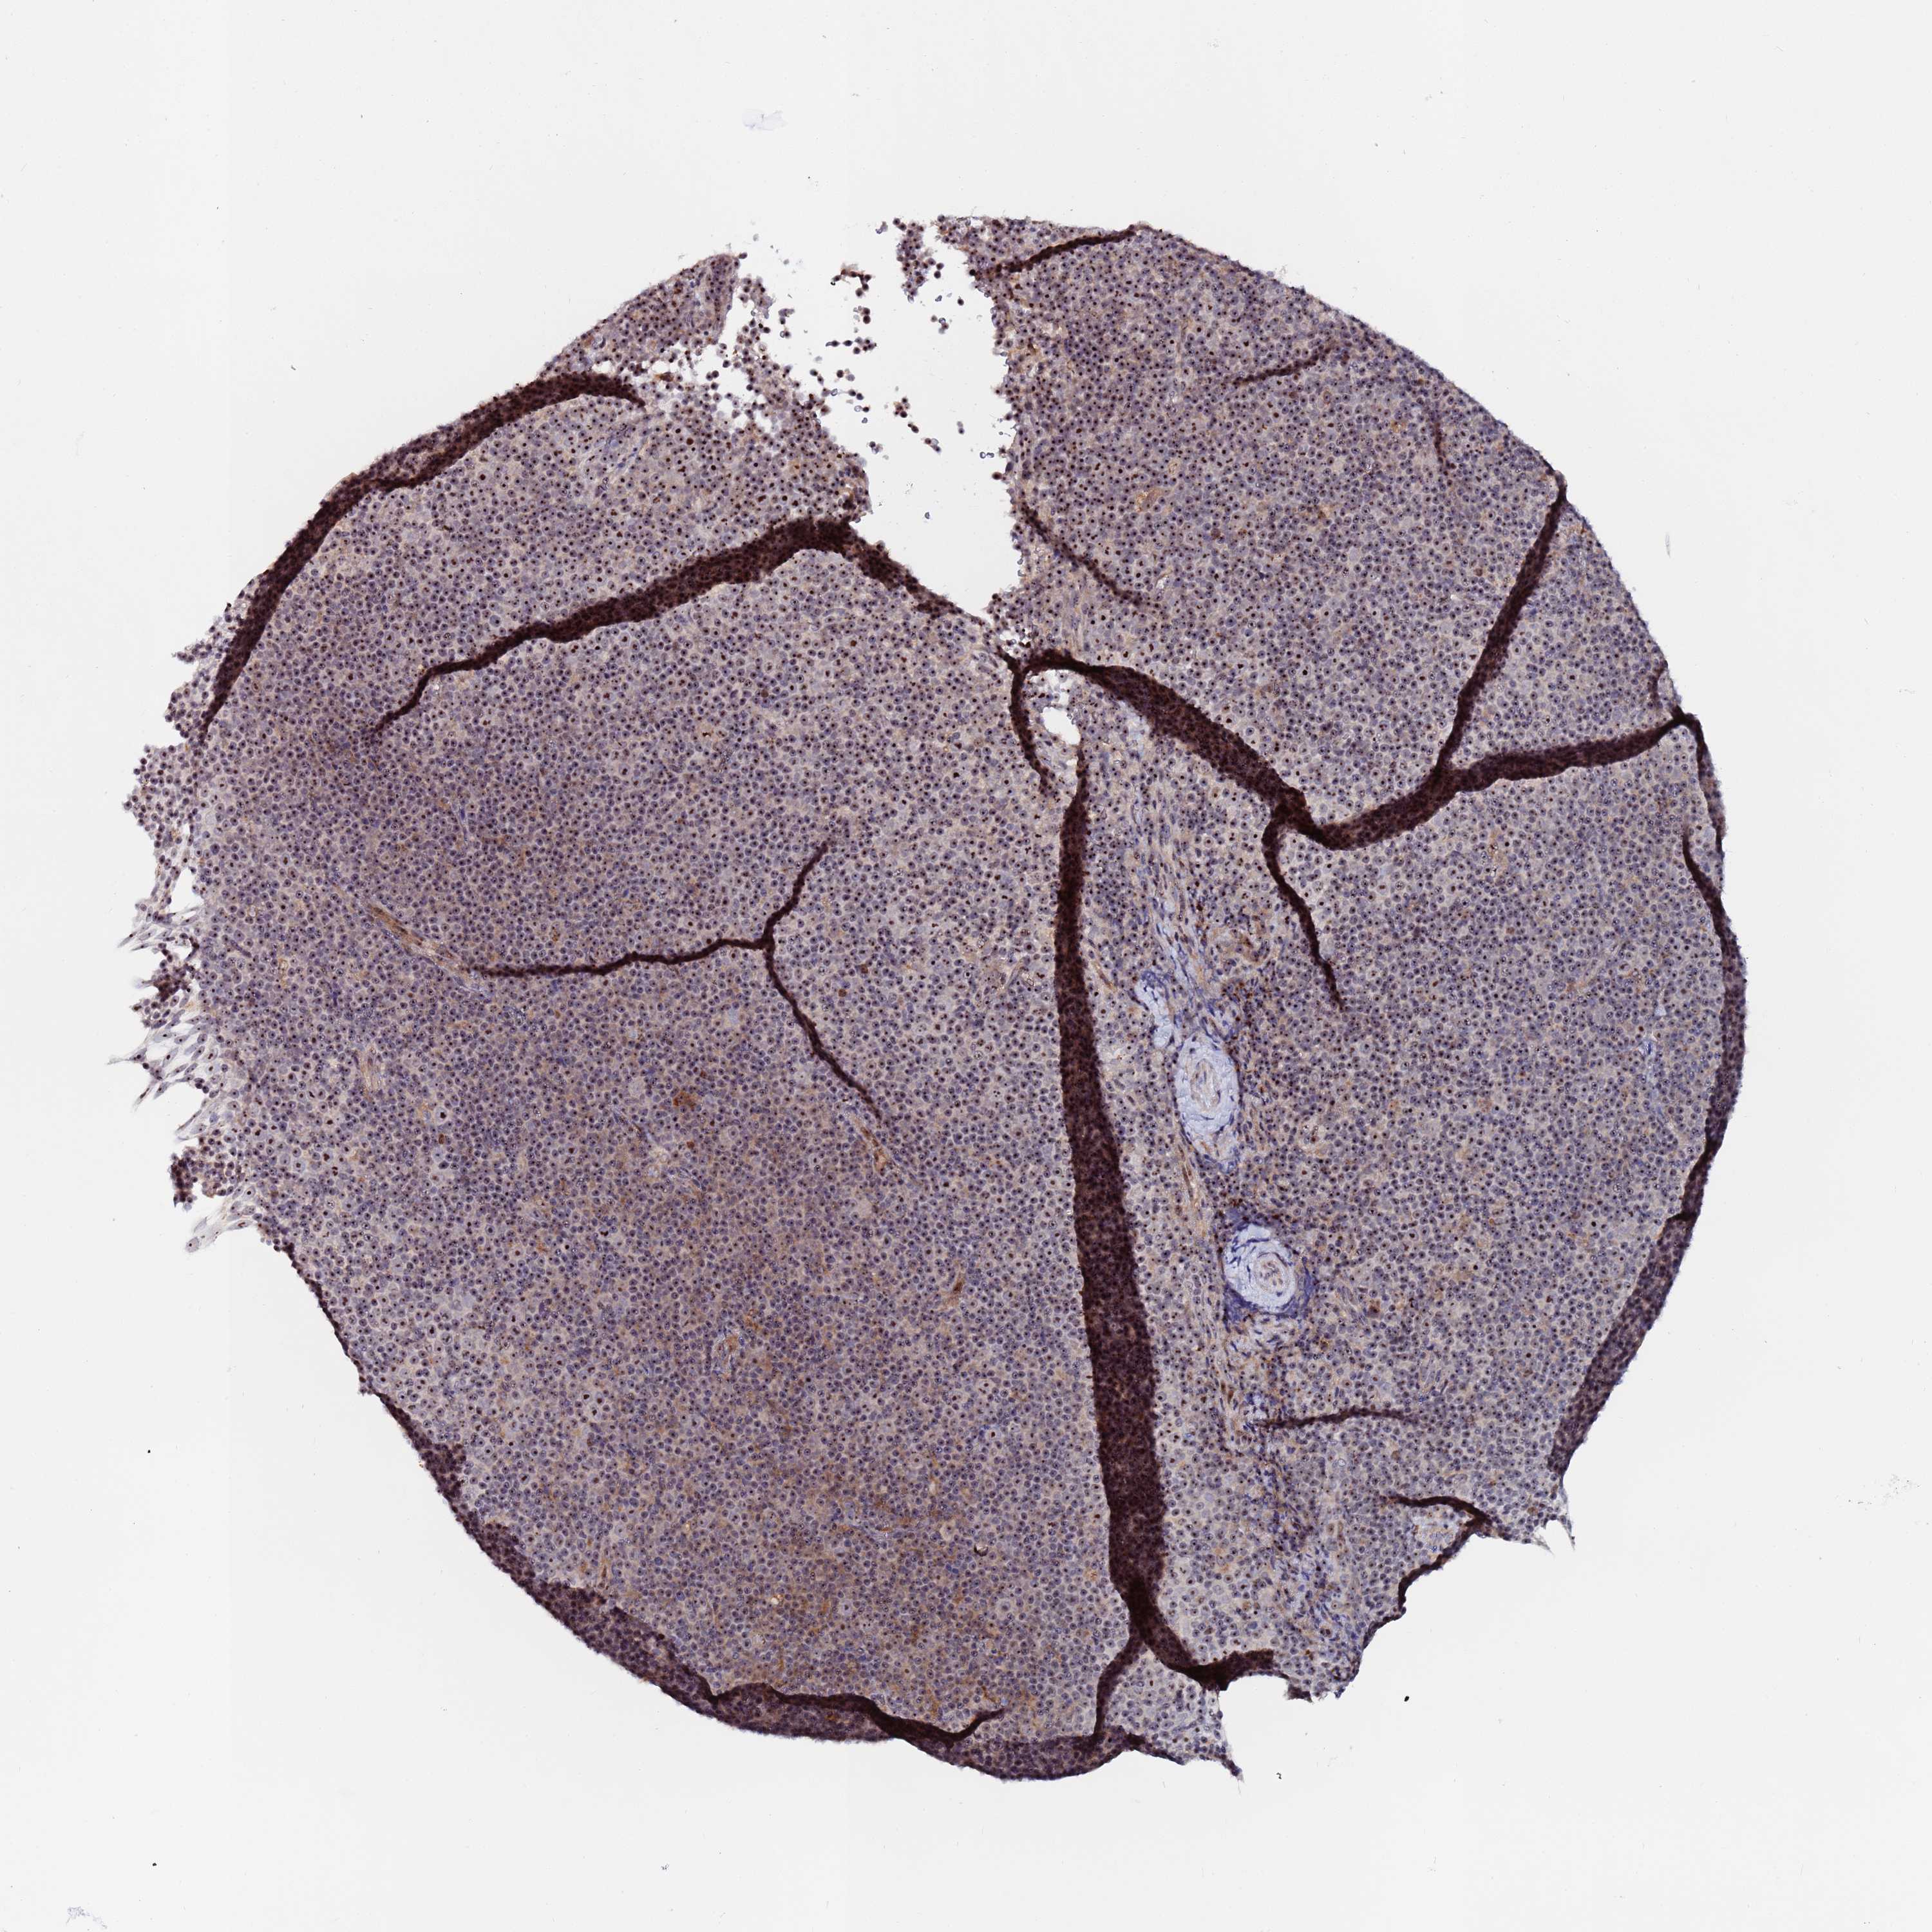

CANCER LYMPHOMA Show tissue menu

LYMPHOMA - Protein expressioni

A mouse-over function shows sample information and annotation data. Click on an image to view it in a full screen mode. Samples can be filtered based on level of antibody staining by selecting one or several of the following categories: high, medium, low and not detected. The assay and annotation is described here.

Each image is clickable and will lead to virtual microscopy that enables deeper exploration of all samples and also displays staining intensity scores, fraction scores and subcellular localization as well as patient and tissue information for each sample.

Antibody HPA043110

Hodgkin's disease, NOS

Malignant lymphoma, non-Hodgkin's type, High grade

Malignant lymphoma, non-Hodgkin's type, Low grade